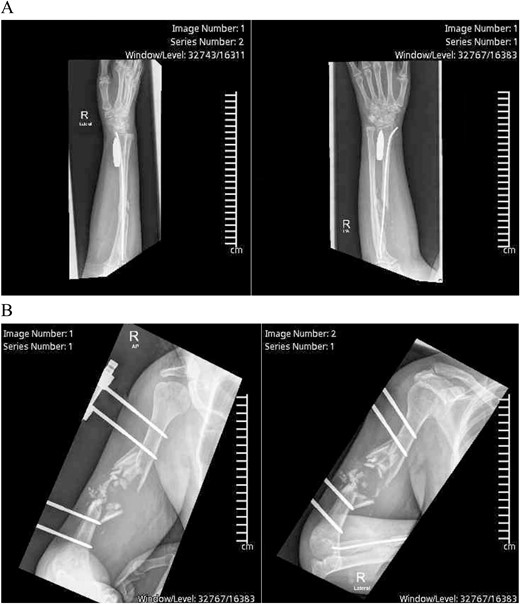

Exploration revealed severe adhesions of radial, median, and ulnar nerves in the proximal 2/3rd third of the arm, adhesions were lesser as the nerves coursed distally in the lower arm and proximal forearm. The radial nerve was completely severed with a marked gap between the distal and proximal ends (Fig. 2). Muscle bellies lying along the bullet tract, at the posterior compartment of arm and volar forearm were charred, fibrotic and replaced by fat. Complete decompression of the peripheral nerves in addition to bullet extraction was performed by Plastic Surgery, with a plan for tendon transfer in regard to the severed radial nerve later on. (Figs 3 and 4) During the surgery, the brachial artery was found severely attenuated, matted to the venae comitantes, and stuck to the bone at fracture site without any recognizable plane in-between, and during adhesiolysis, the artery was inadvertently injured. It was repaired using interposition reversed saphenous vein graft by Vascular Surgery. The patient’s postoperative period was uneventful, with good distal capillary refill and pain control. She was discharged 8 days after the surgery and regularly followed in the outpatient clinic and the hand occupational therapy unit. 3 months follow-up showed significant improvement in sensory symptoms and minimal improvement in motor function.

Intraoperative X-ray showing severe adhesions of the radial, median and ulnar nerves in the proximal 2/3rd of the arm, adhesions were lesser as the nerves coursed distally in the lower arm and proximal forearm.